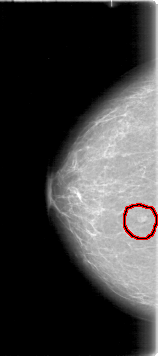

D_4009_1.RIGHT_CC

RIGHT_CC LINES 5326 PIXELS_PER_LINE 2356 BITS_PER_PIXEL 12 RESOLUTION 43.5 OVERLAY

FILE: D_4009_1.RIGHT_CC.OVERLAY

TOTAL_ABNORMALITIES 1

ABNORMALITY 1

LESION_TYPE MASS SHAPE LOBULATED MARGINS OBSCURED

ASSESSMENT 0

SUBTLETY 4

PATHOLOGY BENIGN

TOTAL_OUTLINES 1

BOUNDARY